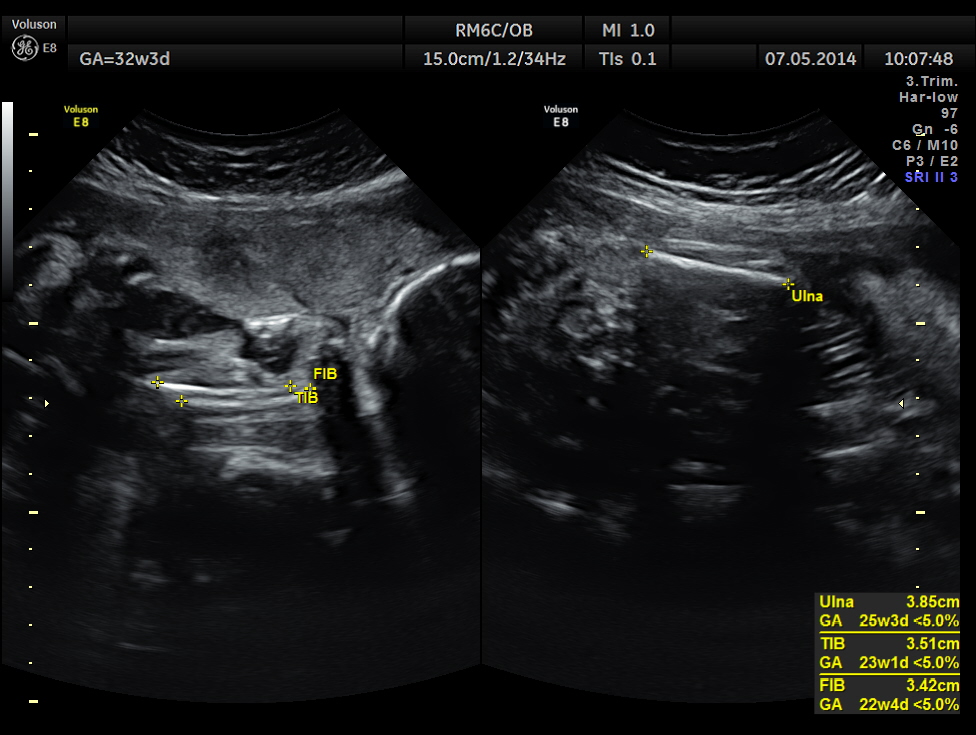

This was a 37 year old lady , a primi gravida referred for evaluation of intra uterine growth restriction. As per LMP the GA was 32 w 3 Days, but as per AUA the GA was 26 weeks . All the long bones were < 5.0 % tile. But cerebellum was 42.7 % tile. There was severe symmetrical growth restriction .

The echo pictures are given below.